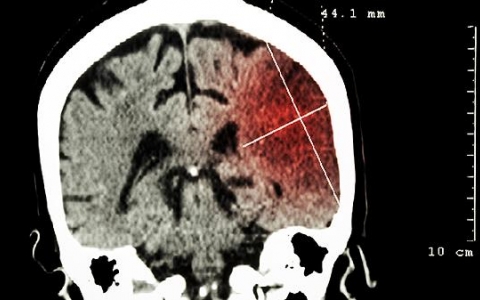

脑溢血临床上指脑出血,脑出血危险期通常为7~15天,如有不适症状,建议及时就医。脑出血属于非外伤性脑实质内出血,患病后会影响脑组织的正常结构与功能,主要表现为语

脑瘤早期什么症状

脑瘤早期的症状一般包括头痛、呕吐、癫痫发作、视觉障碍、精神症状等,如果出现上述症状,建议及时就医。1、头痛:由于脑瘤的占位以及对周围脑组织的牵拉、压迫,会导致颅